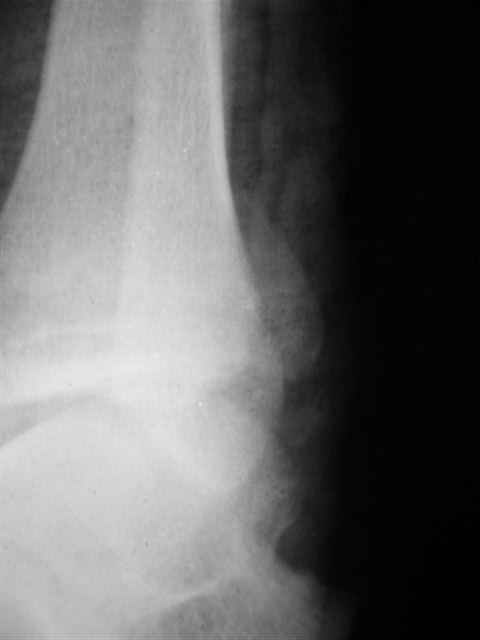

> интересуюсь тактикой лечения повреждений голеностопного сустава.

Ничего сверхъестественного, но если есть интерес, то в понедельник пересниму Рг-граммы и отправлю.

Уважаемый Иван,

Я предупреждал, что ничего сверхъестественного. Каюсь, что одна из спиц прошла несколько дальше, чем нужно было, но главное - перелом стабилизирован и больной работает суставом в полном объёме, несмотря на представленную раннее травму коленного сустава.